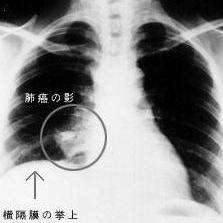

肺部肿瘤片子

肺部肿瘤片子,健康人的肺部ct图片

肺部肿瘤胸片

肺部肿瘤图片

肺部肿瘤x光图片